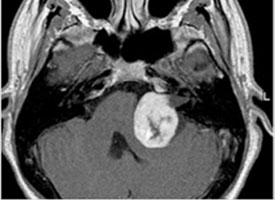

청신경 종양

약1~3% 에서 발견 되므로 MRI 검사를 고려해야 합니다.